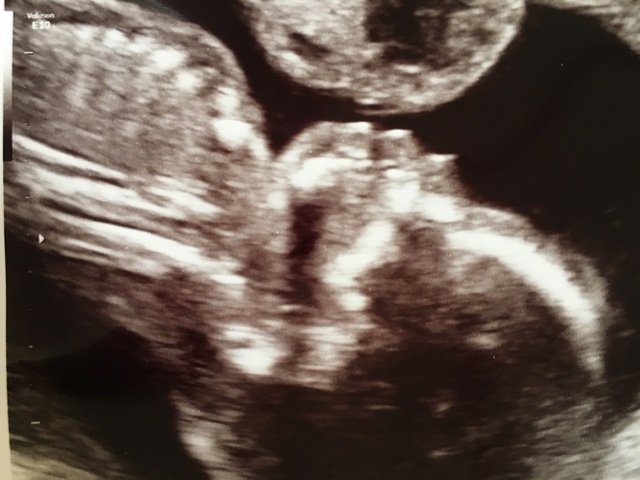

19週5日(19w5d・男の子)|グースケ さん(34歳)

エコー写真撮影時のエピソード:

里帰り出産にする予定で、実家の方の病院を受診した時に双子だと初めてわかりました。ビックリと同時に、二人とも元気で生まれてほしいと願っています。

双子は色々リスクがあるらしく、受診してエコーを撮るたびに二人が同じ様に成長してくれているかとても気になります。